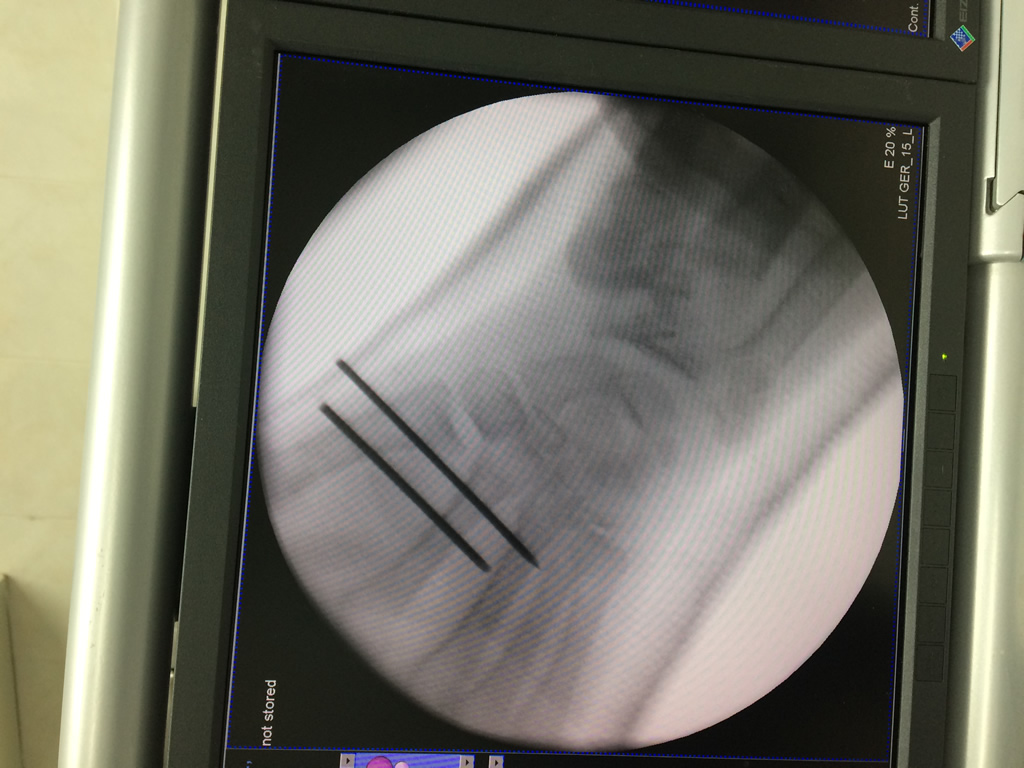

Los procedimientos más comunes en cirugía de la mano son aquellos destinados a reparar traumatismos, incluyendo lesiones de tendones, nervios, vasos sanguíneos, y articulaciones; huesos fracturados; y quemaduras, cortes, y otros daños de la piel.